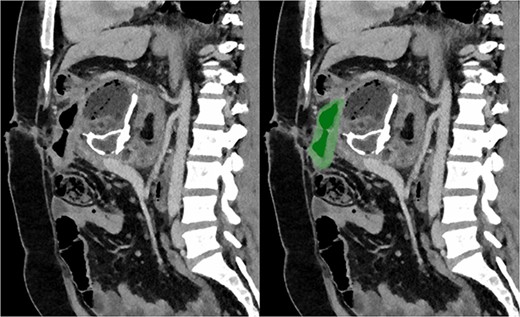

Due to the debilitating nature of the patient’s condition and his wishes for an attempt at treatment, he was brought forward for a further exploratory laparotomy. The patient’s rooftop incision was reopened and the wound and sinus tract were excised en bloc. The stomach and transverse colon were found to be densely adherent to the teratoma. These were carefully mobilized and dissected free from the teratoma. Again, resectability of the teratoma was assessed and deemed to be impossible due to the hepatic artery being inseparable from the lesion (Fig. 2). Instead, internal drainage with diversion of the sinus discharge via a jejunostomy with a Roux en Y reconstruction of the alimentary tract was performed. The jejunum was divided at 50 cm from the duodenojejunal (DJ) flexure and the Roux limb was brought up to the origin of the sinus through a window made in the mesentery of the transverse colon. The lumen was opened and sutured over the origin of the sinus with 4/0 PDS sutures (Fig. 3). Finally, a jejunojejunostomy was formed to return continuity to the jejunum.

Sagittal section of post-operative CT with portal venous contrast demonstrating cystojejunustomy, highlighted in green, anastomosed to the origin of the fistula.